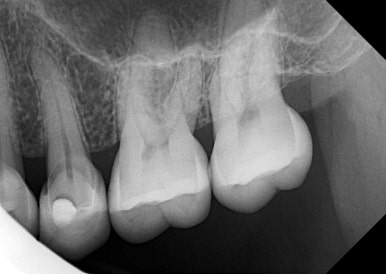

🧑⚕️ 남아 있는 치아는 건강할까?

파절된 보철을 제거한 뒤,

치아 상태를 정밀하게 체크했습니다.

✅ 다행히 치아 뿌리와 구조 모두 건강했고,

✅ 신경치료나 추가 보강 없이 바로 재보철이 가능했어요.